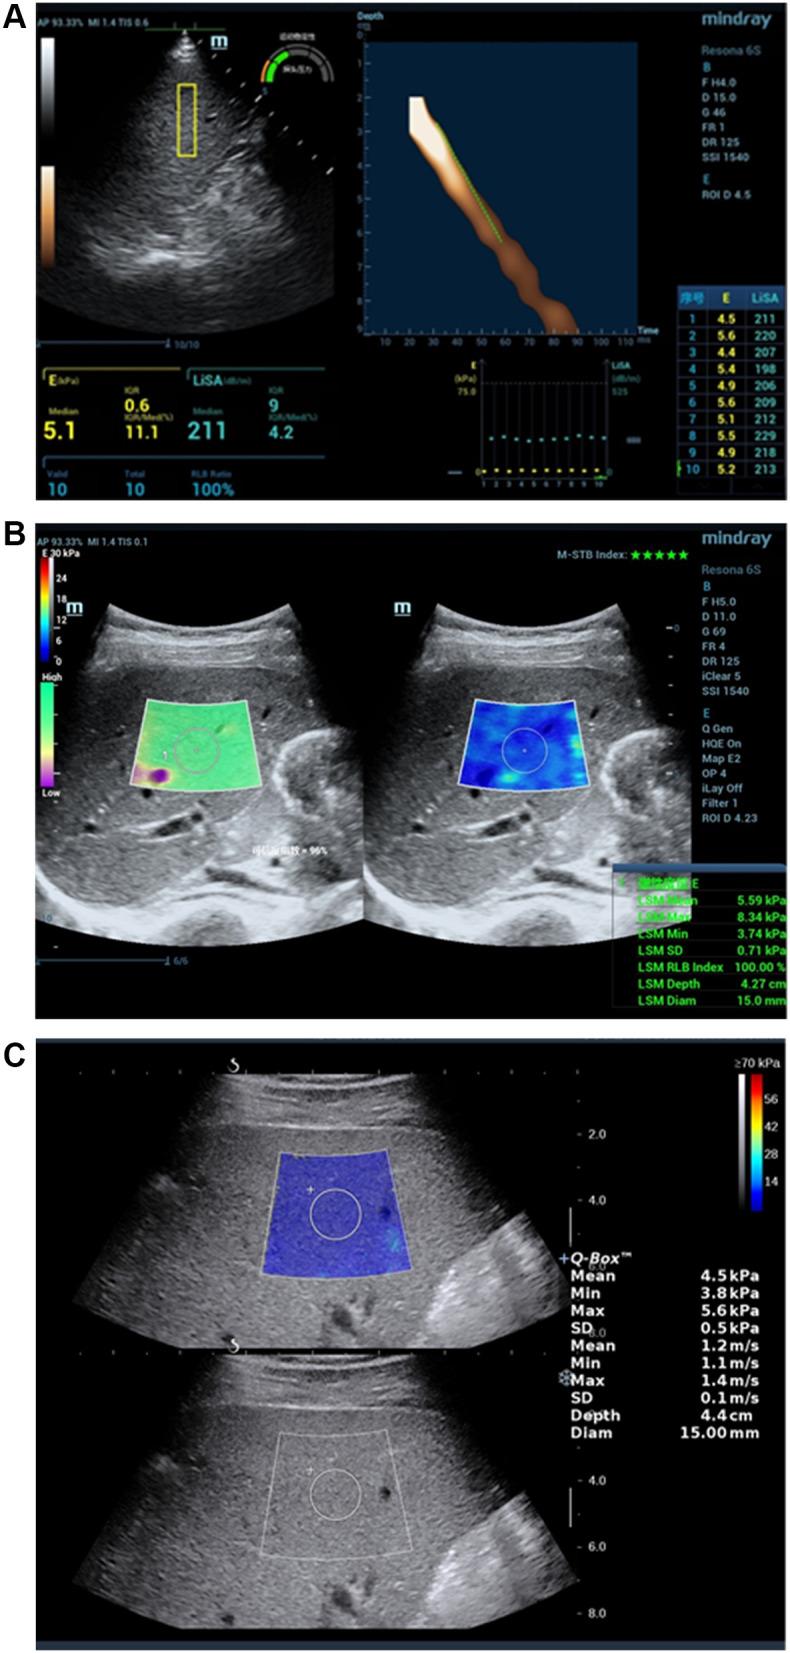

This study investigated the effectiveness and feasibility of shear wave elastography ((sound touch elastography) STE and (shear wave elastography) SWE) and visual transient elastography (ViTE) in the noninvasive quantitative diagnosis of liver fibrosis in chronic liver disease (CLD).

A total of 106 patients with CLD underwent STE, SWE and ViTE elastography evaluation. The Young's modulus of the three elastography was valuated and the diagnostic performances of the three techniques for liver fibrosis staging were compared. The area under the receiver operating curve (ROC) for the diagnosis of liver fibrosis was compared. The final diagnosis was based on the histological findings on the liver biopsy.

1. The correlation between ViTE and SWE, ViTE and STE, SWE and STE stiffness values were 0.72, 0.75, 0.75 (P<0.001). 2) The relationship between the results of each elastography technique and the stage of pathological liver fibrosis showed that the more severe the liver fibrosis was, the higher the stiffness value was (all P <0.001). 3) When the three elastography techniques were used to detect the degree of liver fibrosis in different pathological stages, there was no statistical difference in the stabilities of the boxplots. 4) The ROCs of the three elastography techniques (ViTE, SWE and STE) were 0.88, 0.91, 0.92, F0 vs F1-3; 0.84, 0.84, 0.84, F0-1 vs F2-4; 0.80, 0.79, 0.77, F0-2 vs F3-4; 0.80, 0.76, 0.71, F0-3 vs 4; the AUC of ViTE was higher than the AUC of STE in the identification of F4, but there were no statistical differences in the AUCs of other groups.

ViTE has good stability for the liver stiffness measurement (LSM) and a high consistency with shear-wave elastography (SWE and STE). It is an effective tool for evaluating CLD, and its performance is comparable to SWE and STE. The combination of ViTE and STE can improve the specificity of disease diagnosis and do not add extra cost and may improve cost performance.